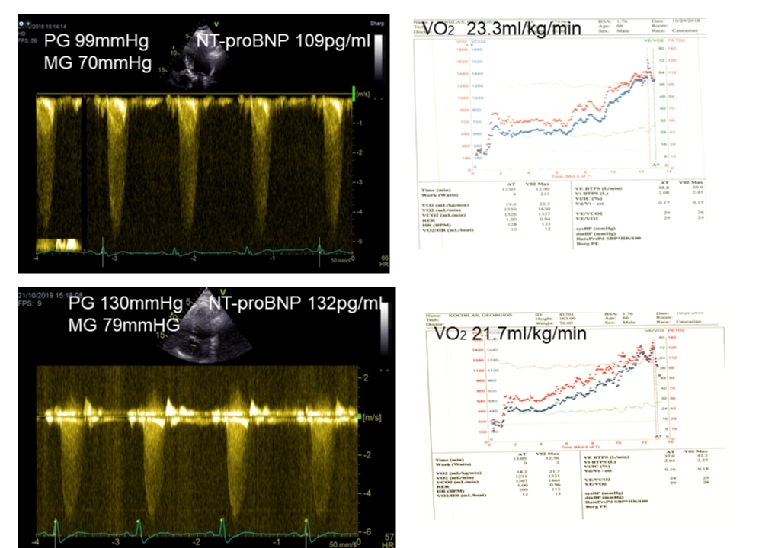

Figure 1. Doppler tracings and cardiopulmonary exercise test results of a 67-year-old asymptomatic patient who refused intervention. The connection of the severity of the disease with exercise capacity and BNP is shown here during follow-up.

Upper Panel: Baseline

Lower Panel: Changes in 12 months’ time. Peak gradient increased by 31 mmHg, O2 consumption decreased from 23.3 ml/kg/min to 21.7 ml/kg/min and NT-proBNP increased from 109 pg/ml to 132 pg/ml (upper normal 125 pg/ml).